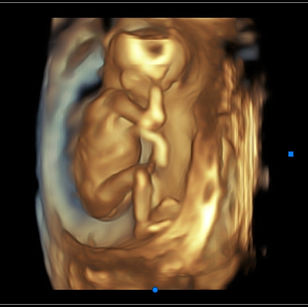

16 Weeks Pregnant

Size: ~4.5 inches (11.5 cm), the size of an Avocado!

16 Weeks 3 Days Pregnant